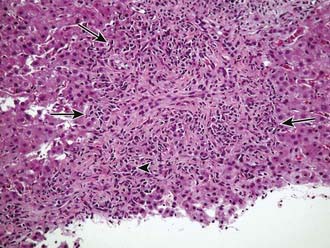

Autoimmune hepatitis is a clinical diagnosis based on certain diagnostic criteria; no single test will make this diagnosis. Diagnostic criteria with scoring systems have been developed for adults and modified slightly for children, although these scoring systems were developed as research and not diagnostic tools. Important positive features include female gender, primary elevation in transaminases and not ALP, elevated gamma-globulin levels, the presence of autoantibodies (most commonly antinuclear, smooth muscle, or liver-kidney microsome), and characteristic histologic findings (Fig. 354-1). Important negative features include the absence of viral markers (hepatitis B, C, D) of infection, absence of a history of drug or blood product exposure, and negligible alcohol consumption.

image

Figure 354-1 Autoimmune hepatitis. Liver biopsy showing fibrous expansion of the portal tracts with moderate portal lymphocytic infiltrates rich in plasma cells (arrowhead). There is extensive interface hepatitis (arrows). Original magnification ×20.

(Courtesy of Margret Magid, Mount Sinai School of Medicine.)

The histologic features common to untreated cases include inflammatory infiltrates, consisting of lymphocytes and plasma cells that expand portal areas and often penetrate the lobule; moderate to severe piecemeal necrosis of hepatocytes extending outward from the limiting plate; variable necrosis, fibrosis, and zones of parenchymal collapse spanning neighboring portal triads or between a portal triad and central vein (bridging necrosis); and variable degrees of bile duct epithelial injury. Distortion of hepatic architecture can be severe; cirrhosis may be present in children at the time of diagnosis. Histologic features in acute liver failure may be obscured by massive necrosis.